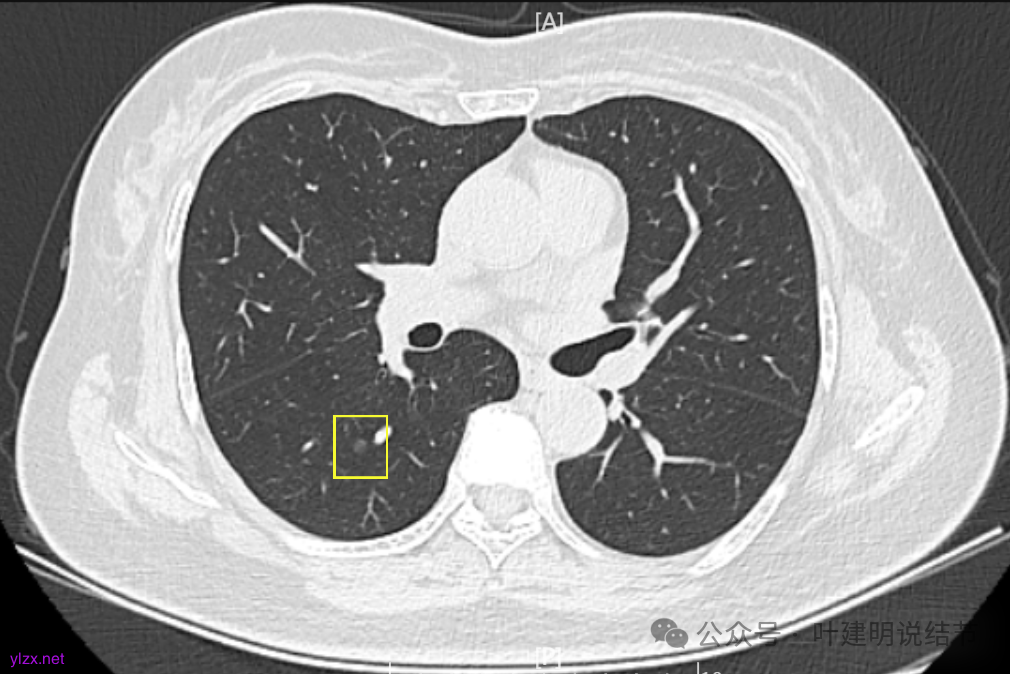

7.2022年11月1日B医院复查ct,显示肺结节0.89*0.51cm。其余变化不大。

8.2023年1月B医院复查ct,显示最大肺结节0.85*0.73cm,其余变化不大。

9.2023年4月复查ct,显示最大肺结节0.79*0.72。2023年3月短暂去某地疗养一月。

10.2023年11月28日复查CT,显示最大结节0.8*0.7cm。

11.2024年9月复查,显示最大结节0.81*0.72。

12.2025年4月复查,显示最大结节0.9*0.7。 另外,看几次报告,多发磨玻璃结节数量在上升,从2022年的3个到2025年的7个。